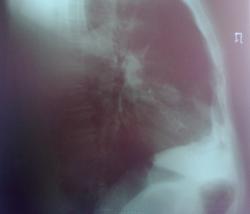

Мужчина лет 50-ти.Жалобы на кашель с мокротой, субфебрильную температуру.Пока лечим пневмонию.

А по-существу тень не очень красивая. На прямой я ее не вижу, может потому что снимок переэкспонированный.

Уважаемый коллега!На прямой тень прилежит практически к корню.Боковые снимки делались в один день( сегодня).Прямой тоже.Первичные снимки от 22.02.2011 сделаны цифровым флюорографом-без динамики.По мне тоже тень не особо привлекательна.

Не рискну трактовать такие снимки - кроме подозрения на расширение правого корня, ничего толком не видно, к сожалению.  Согласна с 1-м постом, контроль после противовоспалительного лечения.

Прямой снимок, конечно, переэкспонирован, боковой ( фотограф из меня никудышный, хотя следовала советам коллег)получился не очень, но, если его не увеличивать, то "тенюшку"на фоне сердечной тени видать хорошо.